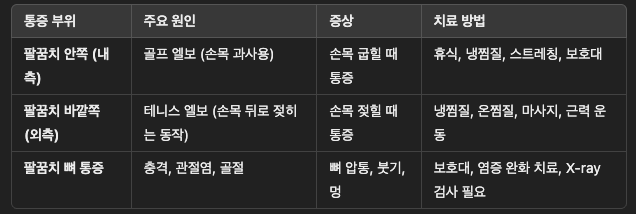

📌 최종 정리: 팔꿈치 통증 원인 & 치료 핵심 요약